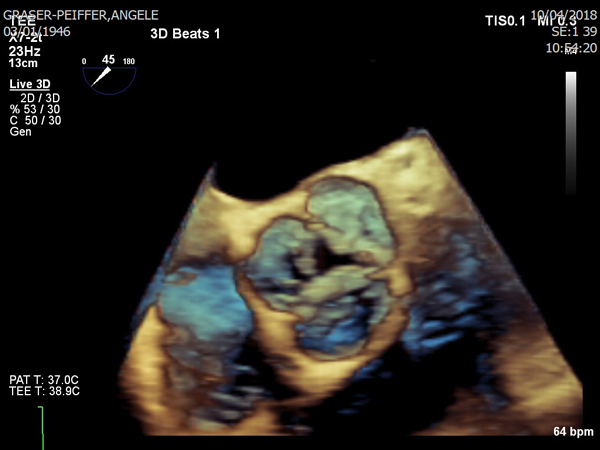

Les symptômes habituels d’une sténose aortique sont des signes de gêne respiratoire (dyspnée), des douleurs thoraciques (angine de poitrine) ou des évanouissements (syncope) sans prodrome, et peuvent apparaître individuellement ou associées. Les problèmes de rythme cardiaque peuvent également être les premiers signes d‘une sténose aortique sévère. En premier lieu, le patient remarque souvent des difficultés liés à l‘effort, par exemple en montant les escaliers ou en montant une pente. Au fil du temps cette fatigue augmente et d‘autres symptômes apparaissent. Il est alors primordial d‘aller consulter son médecin afin d‘éclaircir la cause de ces problèmes. Le médecin procédera à un examen et établira une anamnèse complète. Lors de l‘auscultation du cœur avec un stéthoscope, il perçoit un bruit cardiaque typique qui peut irradier jusque dans les carotides. Ce bruit, qui est décrit comme souffle systolique, est un signe typique d‘une sténose de la valve aortique. Toute suspicion sera confirmée par une échographie du cœur, qui montre clairement si l‘ouverture de la valve aortique est rétrécie et si les feuillets sont calcifiés. On peut mesurer le gradient de pression au dessus de la valve, quand le ventricule gauche essaie par tout moyen d‘éjecter le sang à travers un obstacle rétréci. Si le diagnostic de la sténose aortique est confirmé par l‘échographie normale, on procède souvent avec une échographie trans-œsophagienne, pendant laquelle une sonde à ultrasons est introduite dans l‘œsophage jusqu’au niveau de la paroi postérieure du cœur. Cette méthode permet de bien visualiser et d‘évaluer toutes les valves cardiaques.